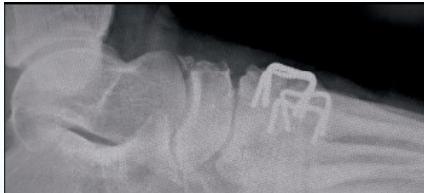

| K-wire (Kirschner Wire) | Indications: Pediatric fractures, small bone fractures in adults. Advantages: Easy to apply/remove. Disadvantages: Not stable alone, risk of infection. | , , , , , ![]() |